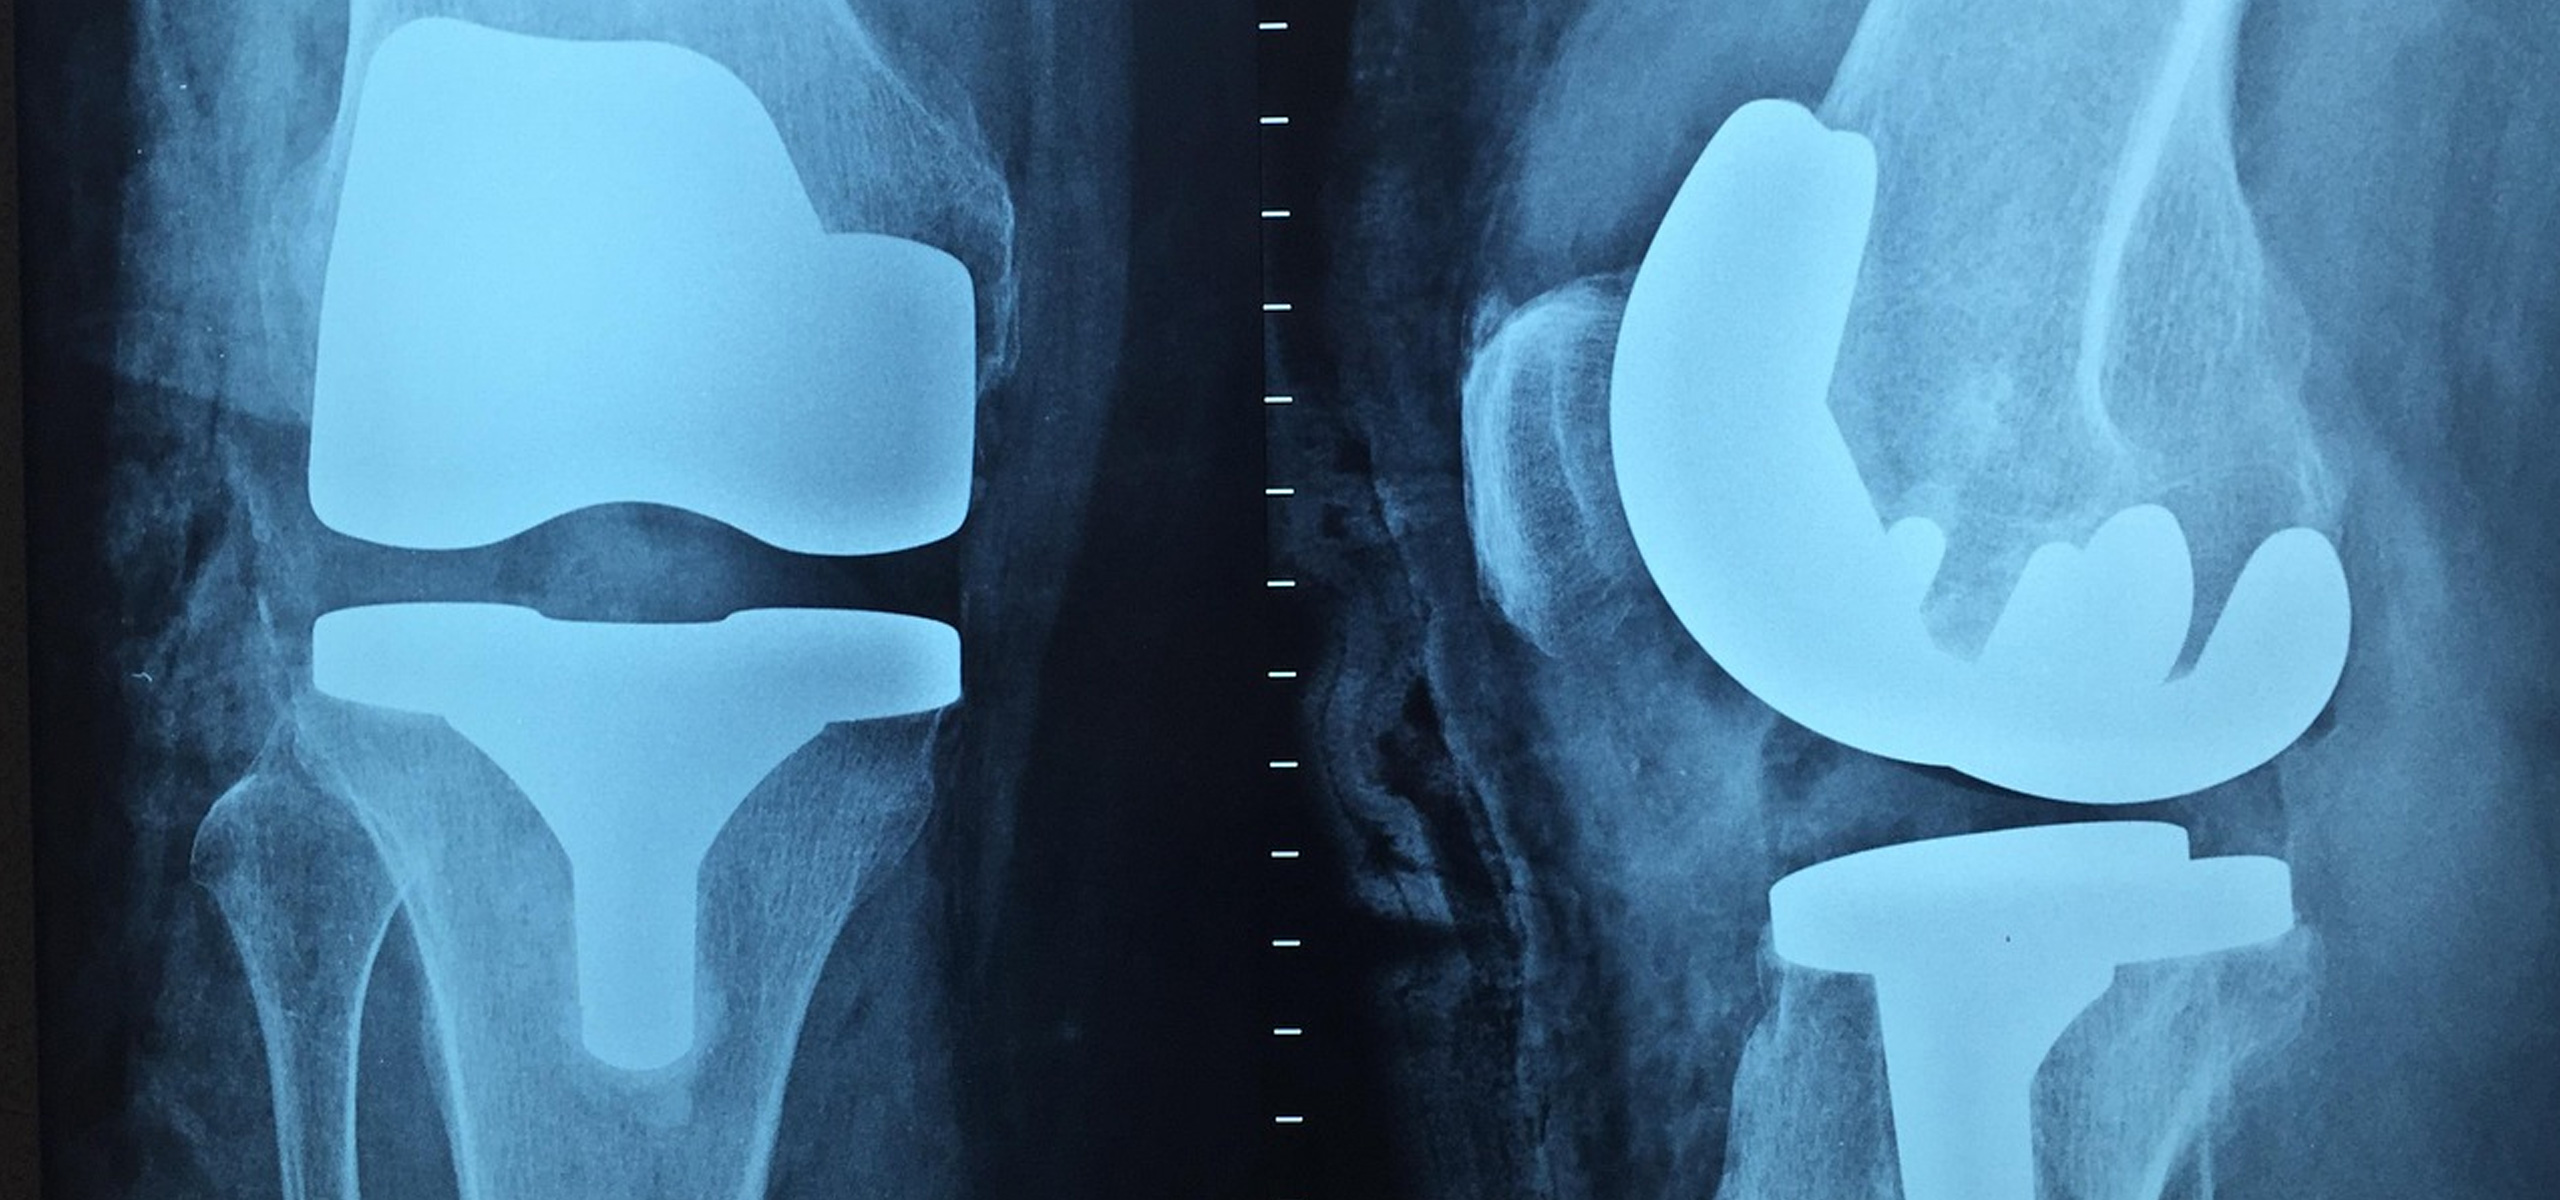

Equipped with modern imaging systems like digital X-rays and MRI (in collaboration), the department ensures accurate diagnosis and swift treatment. We offer a range of services including total knee replacement (TKR), hip replacement, arthroscopy, fracture fixation, and spinal decompression surgeries. Conservative treatments like physiotherapy, pain management, and lifestyle modifications are also integrated for optimal outcomes.